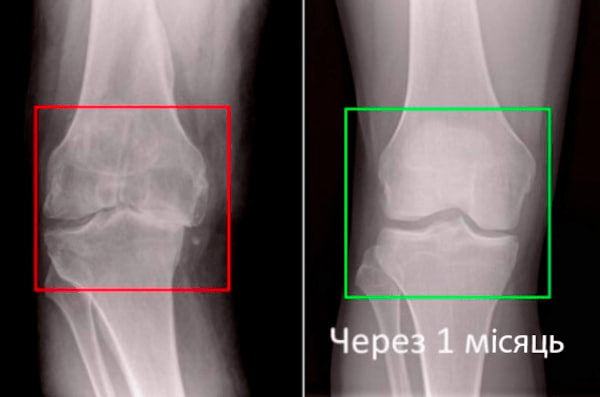

Візьміть до уваги знімок колінного суглоба 63-річного пацієнта за 1 місяць користування Artronil - суглоб повністю регенерувався.